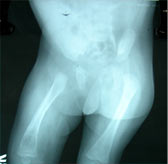

Forearm osteomyelitis